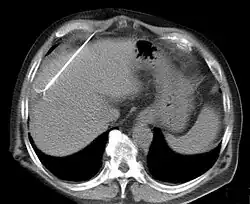

Tomografia komputerowa (TK)

Podstawowym badaniem w wykrywaniu i różnicowaniu raka wątrobowokomórkowego jest wielofazowa spiralna tomografia komputerowa[214]. Konieczne jest uzyskanie obrazu z fazy tętniczej, fazy żyły wrotnej i równowagi. Guz jest bogato unaczyniony głównie poprzez gałęzie z tętnicy wątrobowej, dlatego obraz ognisk raka ulega wzmocnieniu podczas fazy tętniczej lub 2-40 s po infuzji kontrastu[211][214]. Otaczający guz prawidłowy miąższ większość krwi otrzymuje poprzez żyłę wrotną[215], co jest widoczne 50-90 s po infuzji kontrastu (faza wrotna, wrotno-miąższowa)[214]. Część nowotworów jest ubogo unaczyniona, dotyczy to przypadków raka nisko zróżnicowanego oraz wysoko zróżnicowanego we wczesnych postaciach, w których jeszcze nie doszło do rozwoju intensywnego unaczynienia. W tych przypadkach guz jest widoczny w fazie wrotnej. W fazie równowagi można ocenić wiele czynników prognostycznych, w tym obecność torebki rzekomej[214]. Faza tętnicza pozwala wykryć około 95% przypadków raka wątrobowokomórkowego, a faza wrotna około 80% przypadków[216].

Rak w TK cechuje się niejednorodną strukturą, co odzwierciedla zwłóknienie, stłuszczenie, martwicę oraz zwapnienia. Wysycenie nowotworu może różnić się od pozostałego miąższu i wówczas ognisko jest hipodensyjne. Często są obecne zmiany satelitarne[211][214]. Zmiany włókniste lub z torebką wykazują opóźnione wzmocnienie[217].

Trudności diagnostyczne sprawia różnicowanie nowotworu od zmian powstałych w przebiegu marskości wątroby – guzków regeneracyjnych i dysplastycznych. Guzki regeneracyjne w TK są widoczne jako obszary hiperdensyjne, w MRI w obrazach T2-zależnych jako ciemne obszary (hipointensywne). Guzki dysplastyczne cechują się wzmocnieniem kontrastowym w TK i MRI i brakiem wypłukania kontrastu w fazie wrotnej. W przypadku raka dochodzi do szybkiego wypłukania kontrastu przy jednoczesnej obecności wzmocnienia torebki. Nowotwór powstały w guzku dysplastycznym daje obraz wzmocnienia guzka dysplastycznego z jednoczesnym częściowym wypłukaniem kontrastu w obszarze raka – obraz guza w guzie[218].

Angio-TK jest najbardziej przydatnym narzędziem do oceny naciekania naczyń wątrobowych oraz oceny ewentualnych przetok tętniczo-wrotnych i tętniczo-wątrobowych[219][1].